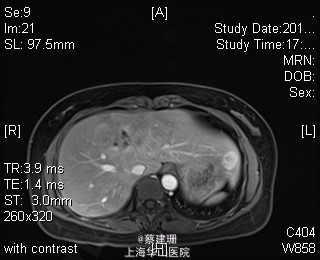

主诉:平滑肌肉瘤、肝转移癌术后,发现肝多发转移2月余。 现病史:患者3年前外院检查发现后腹膜肿瘤,外院行后腹膜肿瘤切除术后,术后病理为:平滑肌肉瘤,2013年12发现肝左叶转移癌,外院行肝左叶肿瘤切除术,术后病理为:梭行平滑肌肉瘤。2月余前患者复查发现肝脏多发转移,2015-4月肝脏MRI:肝脏多发转移。现患者无恶心、呕吐,无呕血、黑便,无皮肤巩膜黄染,无剧烈腹痛发作。现为进一步诊治收住入院。

查体:锁骨上淋巴结未扪及肿大;腹部平坦,可见陈旧性手术疤痕。未见肠型、胃型蠕动波,腹软,无压痛及反跳痛,无肌卫,肝脾肋下未及。Murphy’s 征(-),肝区叩击痛(-),肾区叩击痛(-);移动性浊音阴性。 辅查:2015-4月肝脏MRI:肝脏多发转移。

诊断 :1、多发肝转移癌 2、后腹膜平滑肌肉瘤术后 3、肝转移癌术后 处理:取右侧肋缘下切口,左侧延长,逐层切开进腹,探查腹腔:见上腹部粘连,仔细游离上腹部腹腔粘连,探查见无腹水,胃、肠、胰、脾及盆腔脏器未及异常,腹腔未见明显转移结节;肝脏无硬化。肝门淋巴结无肿大,门静脉主干无栓子。肿瘤多枚,最大两枚位于肝右叶VI段,肿瘤大小约7*6*5cm。V段肿瘤直径约5cm。左内叶肿瘤多枚,直径0.5-4cm,紧贴第一肝门。左外叶肿瘤多枚,直径1-3cm,肿块质韧,边界尚清,有包膜。术中诊断为转移性肝癌,决定行左半肝切除,肝右叶特殊肝段切除。